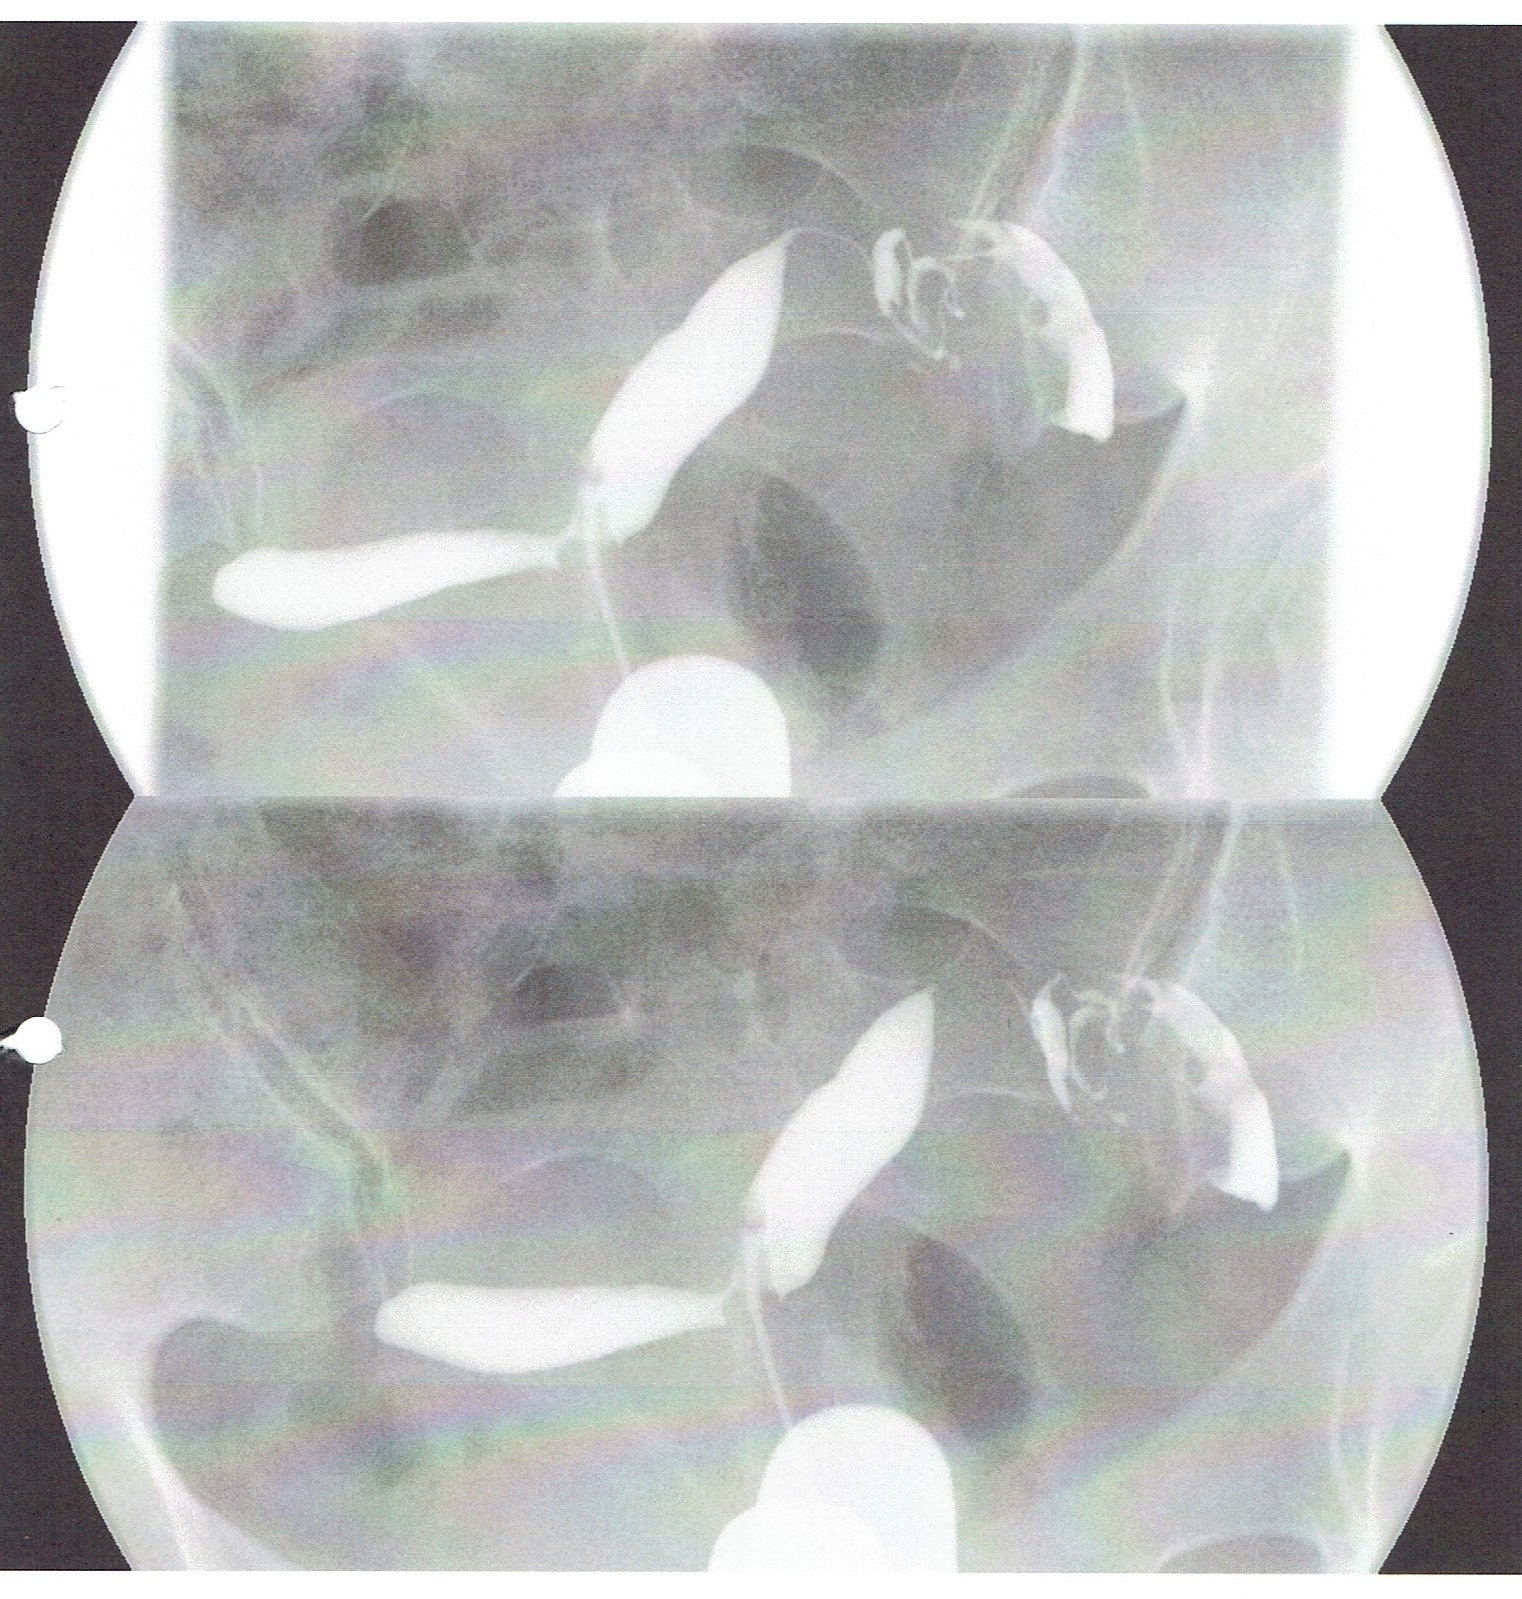

この方は、1年間の治療中断の後、子宮卵管造影検査をおこない、2回目の人工授精で妊娠、卒業となりました。